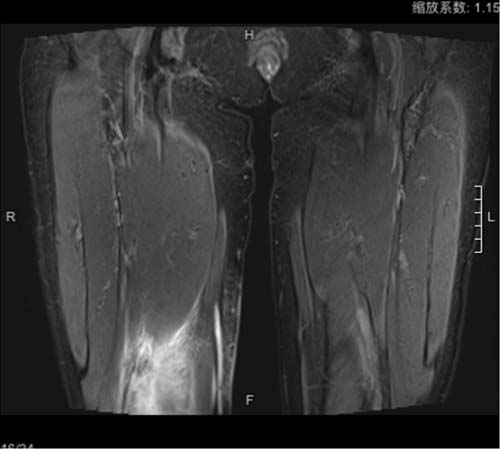

接诊李女士的是皮肤科党宁宁教授。初看皮疹,党宁宁教授发现李女士右侧股内侧浸润性红斑(图2),伴中度硬肿和皮温升高,触痛明显。红肿的皮面,更像是从内向外“洇”出来的。磁共振显示李女士股内侧肌间隙水肿信号(图3)。

图2 右侧大腿浸润性红斑

图3 MR提示右股肌肉间隙水肿信号